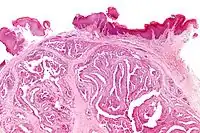

Micrograph of a papillary hidradenoma with the characteristic papillary structures and epithelium with apocrine snouts. A fragmented overlying epidermis is seen at the top of the image. H&E stain.

a,b) Cells of lumina showed decapitation secretion similar to apocrine gland

Intermed. mag.